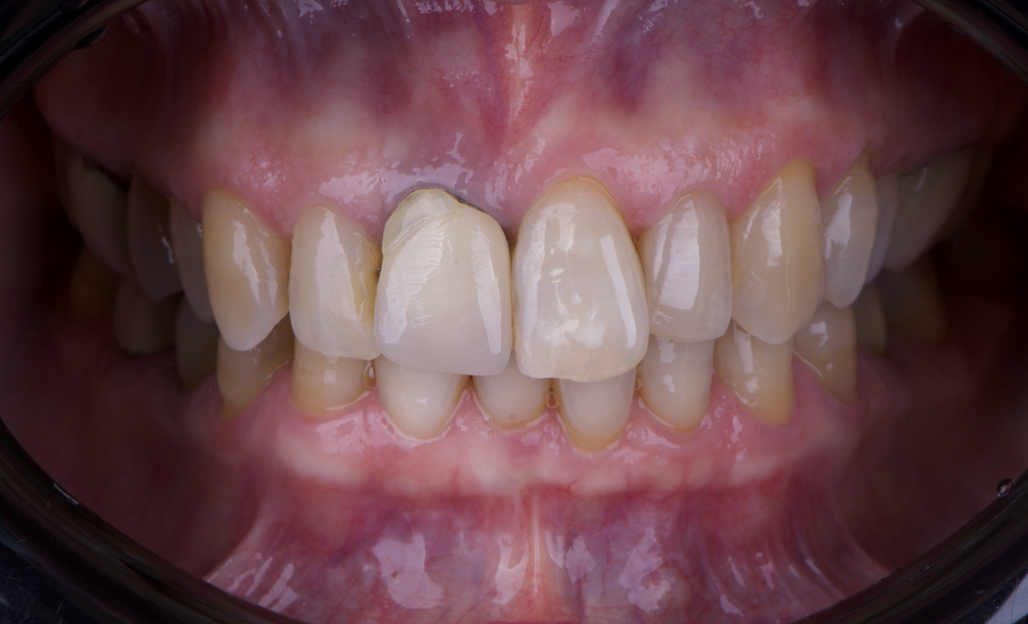

After an appropriate healing period, the definitive prosthesis was planned and delivered. A screw-retained zirconia crown was fabricated to ensure long-term durability, optimal esthetics, and retrievability. Zirconia was selected for its mechanical strength and excellent esthetic properties, blending seamlessly with the adjacent natural dentition in both form and color.

The final crown was designed to maintain the gingival architecture that had been shaped by the provisional. Special attention was paid to the emergence profile, contact points, and translucency to achieve harmony with the patient’s smile. The definitive restoration provided functional stability and esthetic integration, fulfilling the patient’s expectations for a fixed and natural solution.